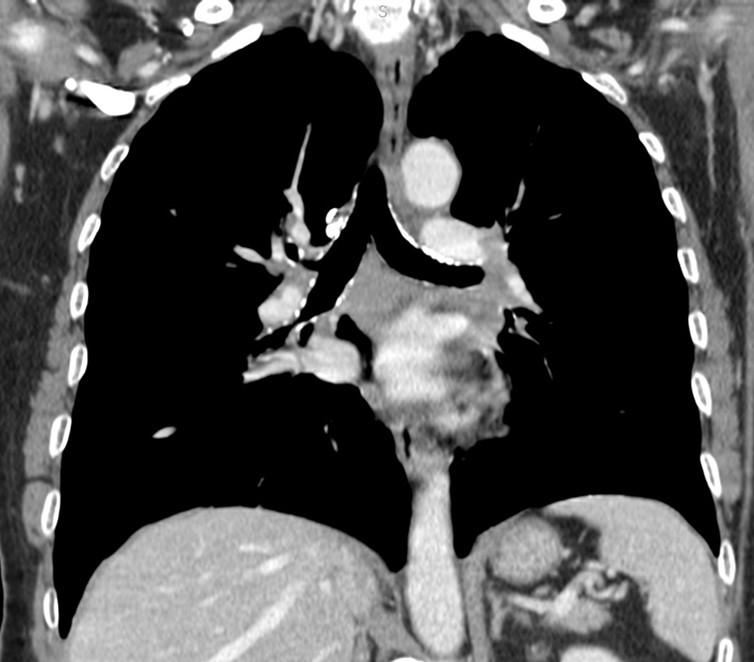

Mosaic attenuation pattern

This pattern appears as patchwork of regions of differing attenuation that may represent (a) patchy interstitial disease, (b) obliterative small airways disease, or (c) occlusive vascular disease. CT features suggesting vascular origin include signs of primary PH, chronic pulmonary embolism, and PVOD.